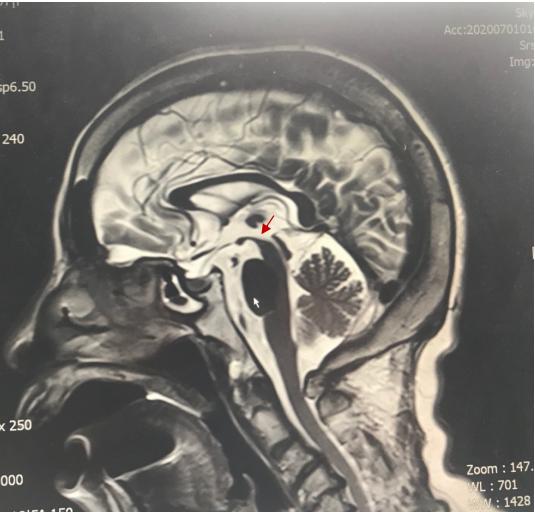

中脑被盖部有萎缩,红色箭头所示 患者头颅磁共振没有典型psp影像

看看中脑的顶盖/被盖示意图